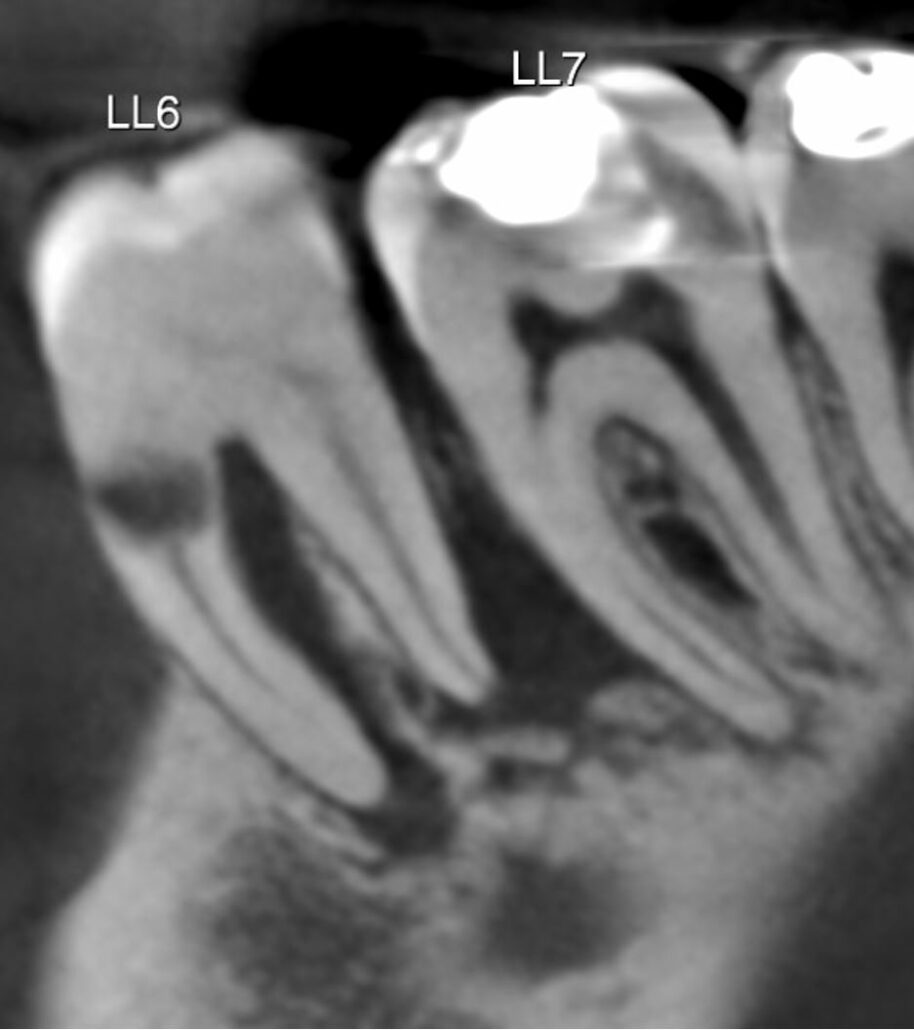

The LL6 mesial-buccal root demonstrates a large root resorption in the cervical third with a wide area of root perforation. There is also another small mesial external resorption.

The LL6 also has periradicular radiolucencies indicating a combined endo-perio lesion. It is most likely unrestorable and has poor prognosis. The inferior dental canal does not contact the LL6 roots.

Image 3